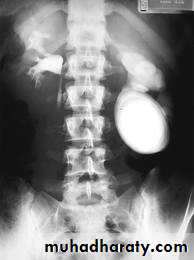

-Plain film may be useful in demonstrating calculi.

-After contrast injection:

Acutely obstructed kidney shows a dense nephrogram (dense opacification of the renal parenchyma).

excretion of contrast (opacification of the collecting system which may take many hours), then the level and degree of obstruction can be determined as dilated pelvi-caliceal system and ureter are followed down to the point of obstruction (point of hold up).

Pyeloxinus reflux may result from rupture of a fornix precipitated by contrast-induced diuresis superimposed on the increased hydrostatic pressure of an obstructed pelvicaliceal system. Urine and contrast extravasate into the renal sinus and perirenal space